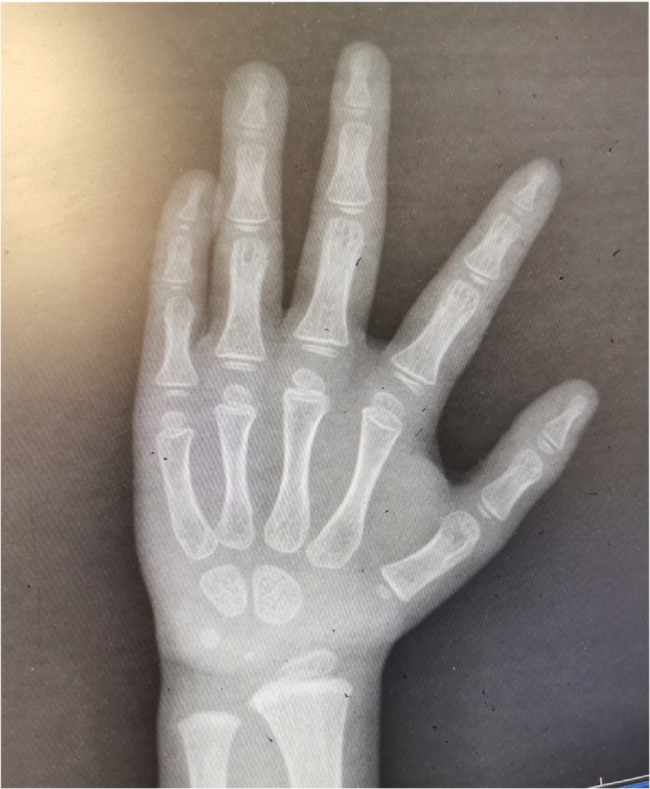

Goltz综合征,又称局灶性真皮发育不全,是一种由PORCN基因突变引起的x连锁显性遗传疾病,主要表现为影响皮肤、头发、骨骼、牙齿和眼睛的发育障碍。本研究报告一例广泛的皮肤发育不良,肢体畸形,身材矮小。1个月大的孩子的基因组DNA全外显子组测序显示PORCN基因突变,证实了戈尔茨综合征的诊断。当她3岁的时候,她的体重下降了

Goltz syndrome, also known as focal dermal hypoplasia, is an X-linked dominant genetic disorder caused by mutations in the PORCN gene, mainly characterized by developmental impairments affecting the skin, hair, bones, teeth, and eyes. This study reports a case with extensive skin dysplasia, limb malformations, and short stature. The genomic DNA whole exome sequencing of the child at 1 month of age revealed a mutation in the PORCN gene, confirming the diagnosis of Goltz syndrome. When she was 3 years old, she suffered from weight loss (W<-3SD) and was short for her age (H<-3SD). The growth hormone stimulation test confirmed growth hormone deficiency. She was treated with long-acting growth hormone (0.2 mg/Kg/week) for 2 years and 9 months, leading to a significant increase in height, with an average annual growth rate of 9.4 cm, without any side effects after three years of follow-up. Goltz syndrome with short stature may be associated with growth hormone deficiency, and long-term growth hormone therapy can achieve clinical benefit.